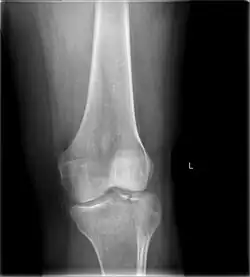

A tibial plateau fracture is a break of the upper part of the tibia (shinbone) that involves the knee joint.[1] This could involve the medial, lateral, central, or bicondylar (medial and lateral).[3] Symptoms include pain, swelling, and a decreased ability to move the knee.[1] People are generally unable to walk.[2] Complication may include injury to the artery or nerve, arthritis, and compartment syndrome.[1]

Diagnosis

In all injuries to the tibial plateau radiographs (commonly called x-rays) are imperative. Computed tomography scans are not always necessary but are sometimes critical for evaluating degree of fracture and determining a treatment plan that would not be possible with plain radiographs.[10] Magnetic Resonance images are the diagnostic modality of choice when meniscal, ligamentous and soft tissue injuries are suspected.[11][12] CT angiography should be considered if there is alteration of the distal pulses or concern about arterial injury.